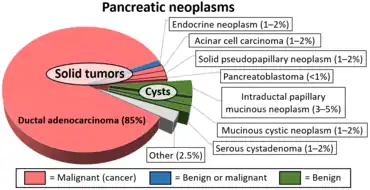

In contrast to some of the other cyst-forming tumors of the pancreas (such as the intraductal papillary mucinous neoplasm and the pancreatic mucinous cystadenoma), serous cystic neoplasms are almost always entirely benign. There are some exceptions; rare case reports have described isolated malignant serous cystadenocarcinomas.[3] In addition, serous cystic neoplasms slowly grow, and if they grow large enough they can press on adjacent organs and cause symptoms.

Pathologists classify serous cystic neoplasms into two broad groups. Those that are benign, that have not spread to other organs, are designated "serous cystadenoma".[5] Serous cystadenomas can be further sub-typed into microcystic, oligocystic (or macrocystic), solid, mixed serous-endocrine neoplasm, and VHL-associated serous cystic neoplasm. This latter classification scheme is useful because it highlights the range of appearances and the clinical associations of these neoplasms. Serous cystic neoplasms that have spread ("metastasized") to another organ are considered malignant and are designated "serous cystadenocarcinoma".

Diagram by Mikael Häggström, M.D.